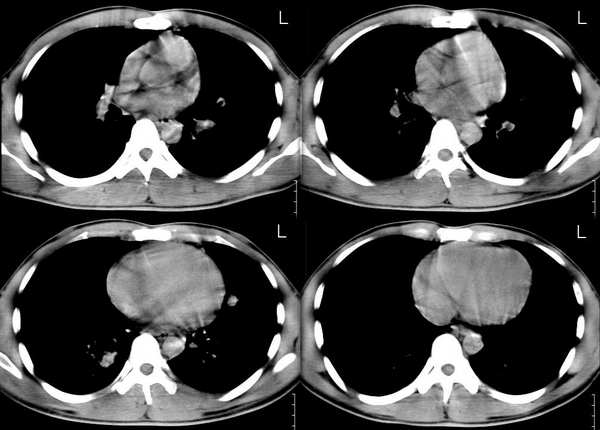

男,21岁,一年前确诊肺结核(未见年前照片),经抗结核治疗出院。2005年9月26日照片与2006年3月1日照片对比,病变反而增多,但病人症状不明显.疑惑?

2005年12月10日照片: